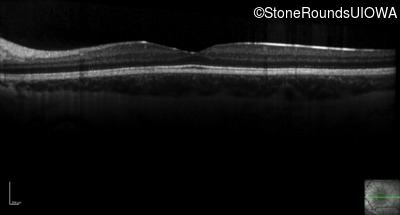

Optical Coherence Tomography - Right - 20/50

Exemplar / OCT Stack